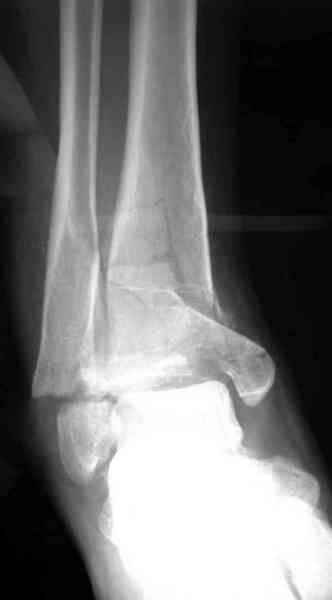

Уважаемые коллеги, оперировать, мне кажется, необходимо. Восстановление суставов, в том числе и столь тяжёлых - не только суть нашей специальности, но и шанс для пациента. В данном случае - молодой женщины. Здесь не нужно ждать результатов КТ - всё понятно и так. Хотите большей ясности - сделайте Ргр без перекрывания металлом плюс добавьте 3/4. Вряд ли стоит откладывать операцию дальше, такие переломы пилона чем раньше оперируешь - тем лучше. Мне кажется, что вряд ли стоит менять классическую пошаговую этапность вмешательства. Дистрактор здесь вряд ли понадобится, кстати. 1й этап - из доступа по заднему краю н\лодыжки отрепонируйте её и фиксируйте 1/3 трубчатой пластиной. Рану не зашивайте. 2й этап. Дальше передним доступом открывайте г\ст сустав, разбирайте *мозаику суставной поверхности*, выстраивайте сустав от наружного фрагмента по тарану, как по матрице. Этот приём всегда использует Виталий Дрягин из Челябинска, признанный эксперт в хирургии этой зоны. Я у него учился. Здесь и неушитый наружный доступ может понадобиться. Суставную поверхность - её отломки - временно фиксируйте спицами и постоянно - винтами. Вот сейчас и, скорее всего, понадобится пластика. И это будет третий этап. И 4й - фиксируйте пластиной - качество кости хорошее, можно и не блокированным *листом клевера*. Есть возможность - блокированной пластиной. Сейчас полно вариантов для пилона. Под ЭОПом контролируйте каждый этап. Раны ушить не забудьте. А главное - не тяните, время уже практически ушло!. И ещё раз - КТ здесь не поможет, а запутать может. Не ждите результатов КТ, сделайте нормальные рентгенограммы и оперируйте. Спасибо. С уважением, Волна

Ув.коллега! С учетом степени разрушения суставных поверхностей, я бы в данном случае рассматривал возможность первичного артродеза, как максимум.

Как минимум ЧКДО и далее артродез. Думаю, что мягкие ткани тоже не в лучшем виде. Прежде чем идти на о/репозицию LCP фиксацию надо оценить возможность мякгих тканей и возможность без проблем уйти из раны, увы, в этой зоне не

Глубокоуважаемый Коваленко А.Н.! По поводу лечения подобных переломов очень хорошо излагал Яков Одесский на Форуме , аргументированно и доказательно ! Почитайте его статью по переломам пилона . И на мой взгляд не стоит открывать зону перелома , потом у Вас будут серьёзные проблемы с мягкими тканями . Вывобите отломки непрямой репозицией , возможно какие то отломки удастся прихватить винтами , а может быть и шилом ( тупым ) чрезкожно получится худо-бедно отрепонировать суставную поверхность . А затем ранние движения и .....Иншаллла , как говорят арабские друзья . Удачи !